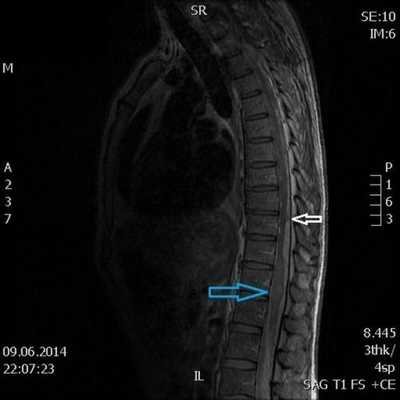

3. Магнитно-резонансная томография (МРТ) с контрастным усилением. На данный момент это основной метод диагностики новообразований спинного мозга. МРТ позволяет визуализировать весь спинной мозг и позвоночник и определить локализацию опухоли. Накопление контрастного вещества определяет не только распространение, но и гистологическую структуру опухоли [5] [6] .

4. КТ-миелография. Применяют для выявления границ опухоли. Метод заключается в контрастировании субарахноидального пространства (полости со спинномозговой жидкостью между мягкой и паутинной оболочками спинного мозга) водорастворимыми веществами. В комбинации с МРТ или КТ позволяет значительно улучшить диагностику опухолей спинного мозга, особенно в окружающих его тканях.

При первых подозрениях пациента направляют на рентген, по снимку которого можно определить, есть ли какие-то затемнения в позвоночнике. Если какие-либо характерные признаки были обнаружены, пациента отправляют на обследование к нейрохирургу и онкологу. В свою очередь они могут назначить обследование на КТ или МРТ для уточнения вида опухоли.

Справка: МРТ (магнитно-резонансная томография) создает снимки не при помощи рентгеновских лучей, а благодаря отраженным электромагнитным импульсам. Снимки получаются трехмерными, и рассматриваемую область можно увидеть в объеме со всех сторон. Является наиболее эффективным методом определения рака.

КТ поможет определить первичные признаки, а МРТ покажет развитие заболевания и распространение метастазов. Также благодаря этому методу диагностики можно увидеть, поражены ли другие органы, а также степень прорастания раковой опухоли из костной ткани в сосуды.